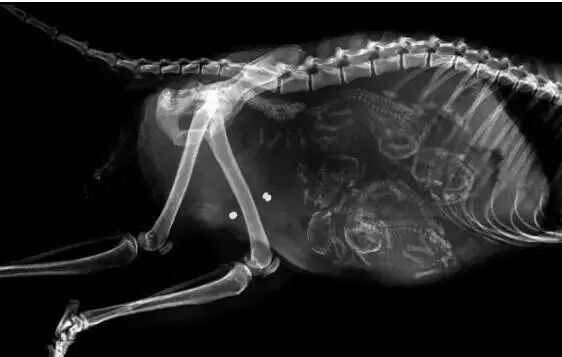

NO.1

<怀孕的狗狗>

虽然知道有些动物,

一次可以孕育很多生命,

但这么拥挤也太夸张了吧!